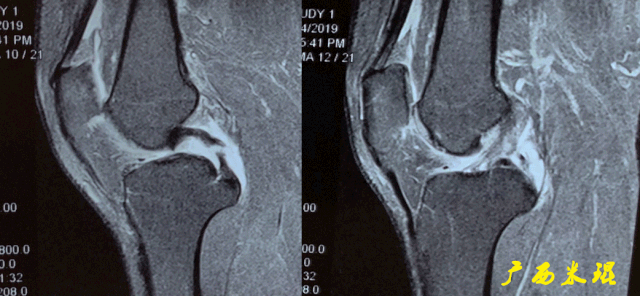

(八)ACL损伤间接征象:

1)ACL撕裂后胫骨前移位出现的一系列改变

2)骨挫伤:

一旦ACL撕裂,胫骨就相对于股骨前移,使股骨外侧髁和胫骨外后方撞击,双方均出现水肿,而且膝关节屈曲的程度决定股骨髁挫伤的部位。

3)沟槽征:

当股骨外髁骨因撞击造成的凹陷深度>2mm时称为沟槽征,代表受到撞击的暴力更大。

6)胫骨前移:

胫骨后缘垂直线位于股骨髁后缘垂直线前方5mm以上。

由于MRI检查时病人为平卧位,胫骨应该因重力而后沉,因此胫骨前移征往往暗示膝关节处于交锁状态。

7)外侧半月板后角裸露征:

外侧半月板后角后缘垂直线位于胫骨后缘皮质垂直线之后方。